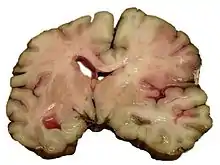

Ictus hemorrágico

Se deben a la rotura de un vaso sanguíneo encefálico debido a un pico hipertensivo o a un aneurisma congénito. Pueden clasificarse en: intraparenquimatosos y hemorragia subaracnoidea.

Las causas más frecuentes en la hemorragia cerebral son la hipertensión arterial y los aneurismas cerebrales.[31]

La hemorragia conduce a ictus a través de dos mecanismos. Por una parte, priva de riego al área cerebral dependiente de esa arteria, pero por otra parte la sangre extravasada ejerce compresión sobre las estructuras cerebrales, incluidos otros vasos sanguíneos, lo que aumenta el área afectada. Ulteriormente, debido a las diferencias de presión osmótica, el hematoma producido atrae líquido plasmático, con lo que aumenta nuevamente el efecto compresivo local. Es por este mecanismo por lo que la valoración de la gravedad y el pronóstico médico de una hemorragia cerebral se demora 24 a 48 horas hasta la total definición del área afectada.